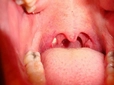

Bademcik ameliyatı sonrası iyileşme süreci kişiden kişiye değişiyor. Genellikle 7-10 gün içinde kendinizi daha iyi hissetmeye başlarsınız. Ancak tam iyileşme için 2-3 hafta geçmesi gerekebilir. Bu süreçte doktorun önerilerine uymak önemli.

Bademcik Ameliyatı Sonrası İyileşme Süreci

Yalkın, bahsettiğin gibi bademcik ameliyatı sonrası iyileşme süreci kişiden kişiye değişebiliyor. Genellikle 7-10 gün içinde kendimizi daha iyi hissetmeye başlasak da, tam anlamıyla iyileşmek için 2-3 hafta beklemek gerekebiliyor. Bu süreçte, özellikle doktorun önerilerine uymak oldukça önemli.

İyileşme Sürecinde Dikkat Edilmesi Gerekenler

İyileşme sürecinde bol sıvı tüketimi, yumuşak gıdalarla beslenme ve dinlenme ön planda olmalı. Ayrıca, ağrı kesici kullanımı konusunda doktorun tavsiyelerine uymak da rahatlamanıza yardımcı olacaktır.